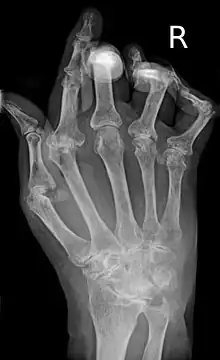

La artritis o inflamación de las articulaciones es la manifestación fundamental de la artritis reumatoide. Las articulaciones afectadas están hinchadas, calientes, dolorosas y rígidas, en especial al levantarse por la mañana o tras el reposo prolongado. Al principio pueden estar afectadas solo una o varias articulaciones, pero progresivamente se van sumando más articulaciones inflamadas —poliartritis—, siendo las que con más frecuencia se afectan las pequeñas articulaciones de las manos y los pies, aunque también es frecuente la afectación de otras articulaciones más grandes como los codos, los hombros, las rodillas o los tobillos.[48] La rigidez matinal es, con frecuencia, un dato destacado de la enfermedad y suele durar más de una hora. Estos datos ayudan a distinguir a la artritis reumatoide de otros problemas no inflamatorios de las articulaciones, como la artrosis u otros tipos de artritis. Las articulaciones se afectan habitualmente de un modo simétrico —afectando articulaciones semejantes en ambos lados del cuerpo—.[49] A medida que la enfermedad progresa, la inflamación articular causa erosiones y destrucción de las superficies articulares y daños tendinosos. Los dedos de las manos pueden sufrir diversas deformidades dependiendo de qué articulaciones y estructuras son las más lesionadas. Son deformidades típicas de la artritis reumatoide evolucionada los dedos en cuello de cisne, la deformidad en ráfaga cubital, la deformidad en boutonniere y el pulgar en Z.[48] La inflamación articular mantenida puede originar daños estructurales en las articulaciones, causando deformidad y pérdida funcional de la articulación afectada.[50][51]

La radiografía convencional es la técnica de imagen estándar de la artritis reumatoide. Los primeros signos radiológicos son la osteoporosis yuxtaarticular y el aumento de partes blandas. Estos cambios se siguen de la disminución del espacio articular, que corresponde a la pérdida de cartílago articular, y la aparición de erosiones óseas en las zonas adyacentes al cartílago articular. El tiempo mínimo para la detección de cambios estructurales en las radiografías está entre 6 y 12 meses, detectándose erosiones radiológicamente en el 50% de los pacientes en el primer año de la enfermedad.[49] En la práctica clínica se utilizan las radiografías para el diagnóstico de la enfermedad, para valorar la gravedad del daño articular y para evaluar su progresión. El ultrasonido y la resonancia magnética son técnicas más sensibles que la radiología convencional.